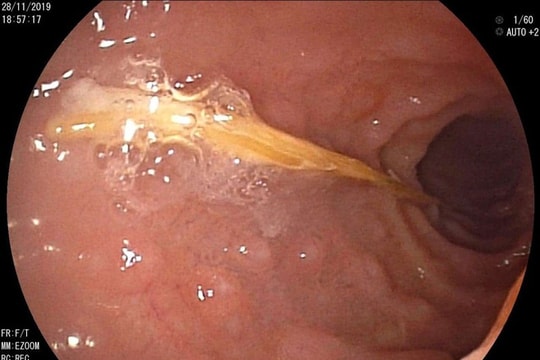

Ăn lẩu, nam bệnh nhân bị xương cá đâm thủng ruột

Người đàn ông nhập viện cấp cứu trong tình trạng bụng đau quặn từng cơn và sốt được các sĩ xác định bị chiếc xương cá dài 2,5 cm đâm thủng ruột.